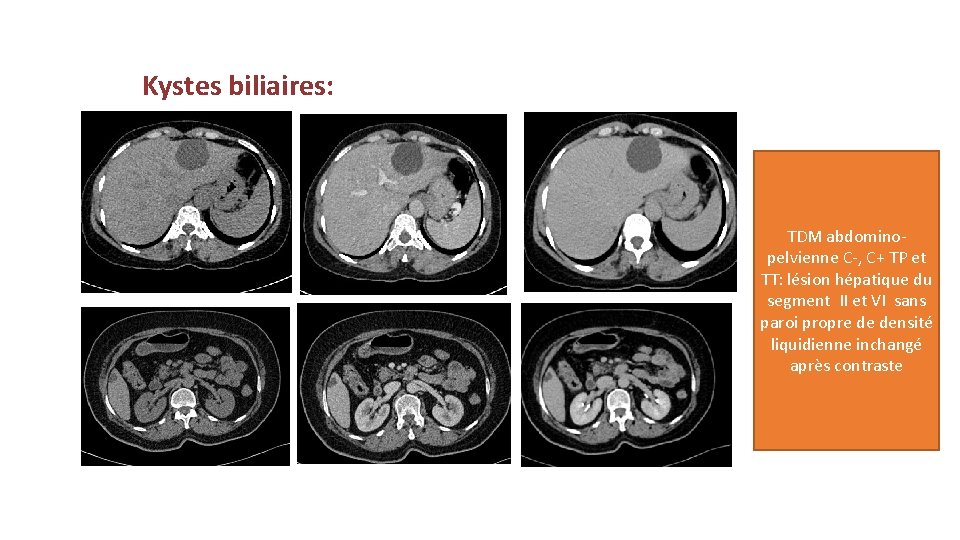

Kystes biliaires: TDM abdominopelvienne C-, C+ TP et TT: lésion hépatique du segment II et VI sans paroi propre de densité liquidienne inchangé après contraste

Kyste biliaire • Il s’agit de la lésion bénigne la plus fréquente. Ils peuvent être unique ou multiples et mesurent de quelques mm à plusieurs cm de diamètre. • Ces lésions peuvent se compliquer si elles sont grandes de taille: saignement, compression, surinfection, rupture. • Échographie: lésion anéchogène, ovalaire, à bord net, à paroi invisible. La paroi n’est jamais calcifiée. • Scanner: hypodense avant injection et ne se rehausse pas après injection de produit de contraste. La paroi est très fine. • IRM: hypersignal en T 2 pondérée de type liquidien et hyposignal en T 1 sans modification après contraste. • • L’échographie suffit pour poser le diagnostic des kystes biliaires. • Diagnostic différentiel: KH ( type I), métastases kystiques.